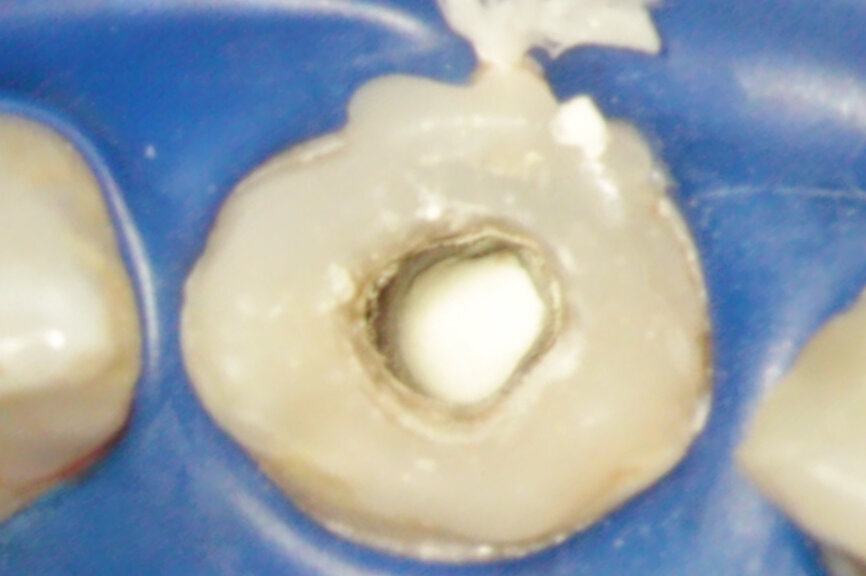

Vital pulp therapy has become more popular in recent years. Calcium hydroxide has been the most common material for pulp capping, but MTA has shown even better results in biocompatibility and outcome.[3] Cases with large carious pulp exposure can be treated successfully with partial pulpotomy and MTA as a capping agent, keeping teeth vital (Figs. 1a–e).

Fig. 1a: (a) Deep carious lesion. (b) Partial pulpotomy. (c) MTA application with the MAP System and PD MTA White. (d) Filling. (e) Post-op radiograph showing the pulp capping with MTA.

Fig. 1b: (a) Deep carious lesion. (b) Partial pulpotomy. (c) MTA application with the MAP System and PD MTA White. (d) Filling. (e) Post-op radiograph showing the pulp capping with MTA.

Fig. 1c: (a) Deep carious lesion. (b) Partial pulpotomy. (c) MTA application with the MAP System and PD MTA White. (d) Filling. (e) Post-op radiograph showing the pulp capping with MTA.

Fig. 1d: (a) Deep carious lesion. (b) Partial pulpotomy. (c) MTA application with the MAP System and PD MTA White. (d) Filling. (e) Post-op radiograph showing the pulp capping with MTA.

Fig. 1e: (a) Deep carious lesion. (b) Partial pulpotomy. (c) MTA application with the MAP System and PD MTA White. (d) Filling. (e) Post-op radiograph showing the pulp capping with MTA.